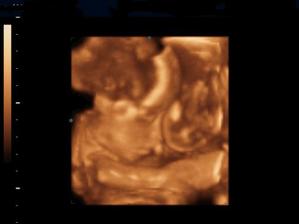

Naše kinderka

Dňa 24.8.2009 o 9.15 sa nám sekciou narodili naše krásne dvojičky Vanesska 2280 g a Larinka 2990 g. Robia nám veľkú radosť a moc ich ľúbime...